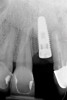

Clinical examination showed 2 mm of buccal recession with a shallow vestibule and absence of keratinized attached gingiva against the crown with 8 mm of circumferential pocketing accompanied by bleeding upon probing (Figure 15 and Figure 16). A periapical radiograph showed a symmetrical vertical osseous defect causing the loss of 50% of the bone around the implant (Figure 17). Because the patient had made a significant investment of time and finances to replace her lost tooth with the implant, she desired that the implant and restoration be retained, if feasible.

Fig 17. Radiograph showed symmetrical infrabony defect affecting 50% of the implant surface.

Figure 17